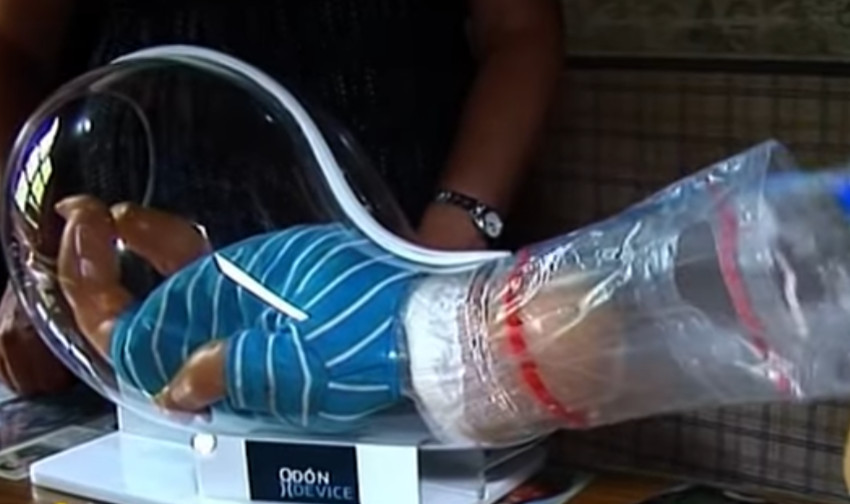

Ako primetite da vam prsten postaje tesan, najbolje je da reagujete na vreme. Nemojte čekati da prsti dodatno oteknu. Pokušajte da ga skinete kada su ruke najmanje otečene, obično ujutru ili nakon odmora. Možete koristiti sapun, ulje ili kremu kako biste olakšale skidanje, uz lagano i strpljivo pomeranje prstena.

U situacijama kada prsten više ne može da se skine, važno je da ne forsirate na silu, jer to može dovesti do povrede ili dodatnog oticanja. U tom slučaju, pomoć mogu pružiti stručna lica, zlatar ili medicinsko osoblje, koji imaju alate za bezbedno uklanjanje prstena.